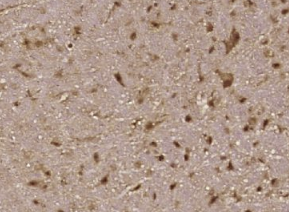

多聚甲醛固定,石蜡包埋(小鼠脑);用柠檬酸钠缓冲液(PH6.0)煮沸15min;用3%过氧化氢阻断内源过氧化物酶20分钟;阻断缓冲液(正常山羊血清)37℃30min;用磷酸-B-RAF(Ser4)孵育抗体。46))多克隆抗体,未结合,1:400,4°C下过夜,然后根据SP试剂盒(兔子)说明和DAB染色进行操作。